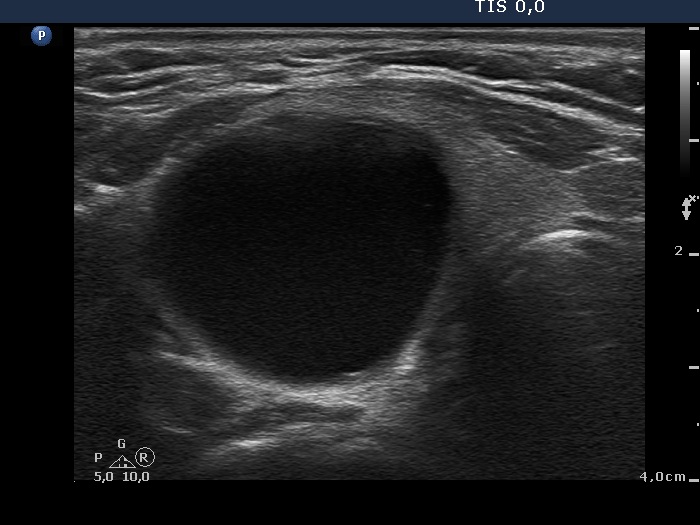

Ultrasonography. The thyroid was echonormal. There was large cyst in the right lobe. The cyst seemed to be a peripheral-type lesion with an inhomogeneous solid part having numerous hyperechogenic figures which belonged to the non-specific category. There were two hyperechogenic lesions in the right while a moderately hypoechogenic one in the left lobe.